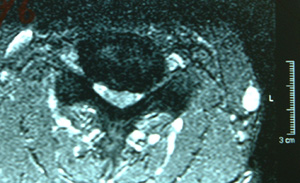

| MRI画像(東京女子医科大学整形外科提供) | ||

| 手術前 | 手術後 | |

| 縦断面(中心) | ![]() |

| 所見 | 頸椎ジョイント部で狭窄が顕著。脊髄と脊柱管の間の余裕がない。部分的に、脊髄内部に血行障害が認められる。 | 脊柱管は拡大され脊髄は自由に位置している。脊髄と脊柱管の間の余裕も確保されている。 |